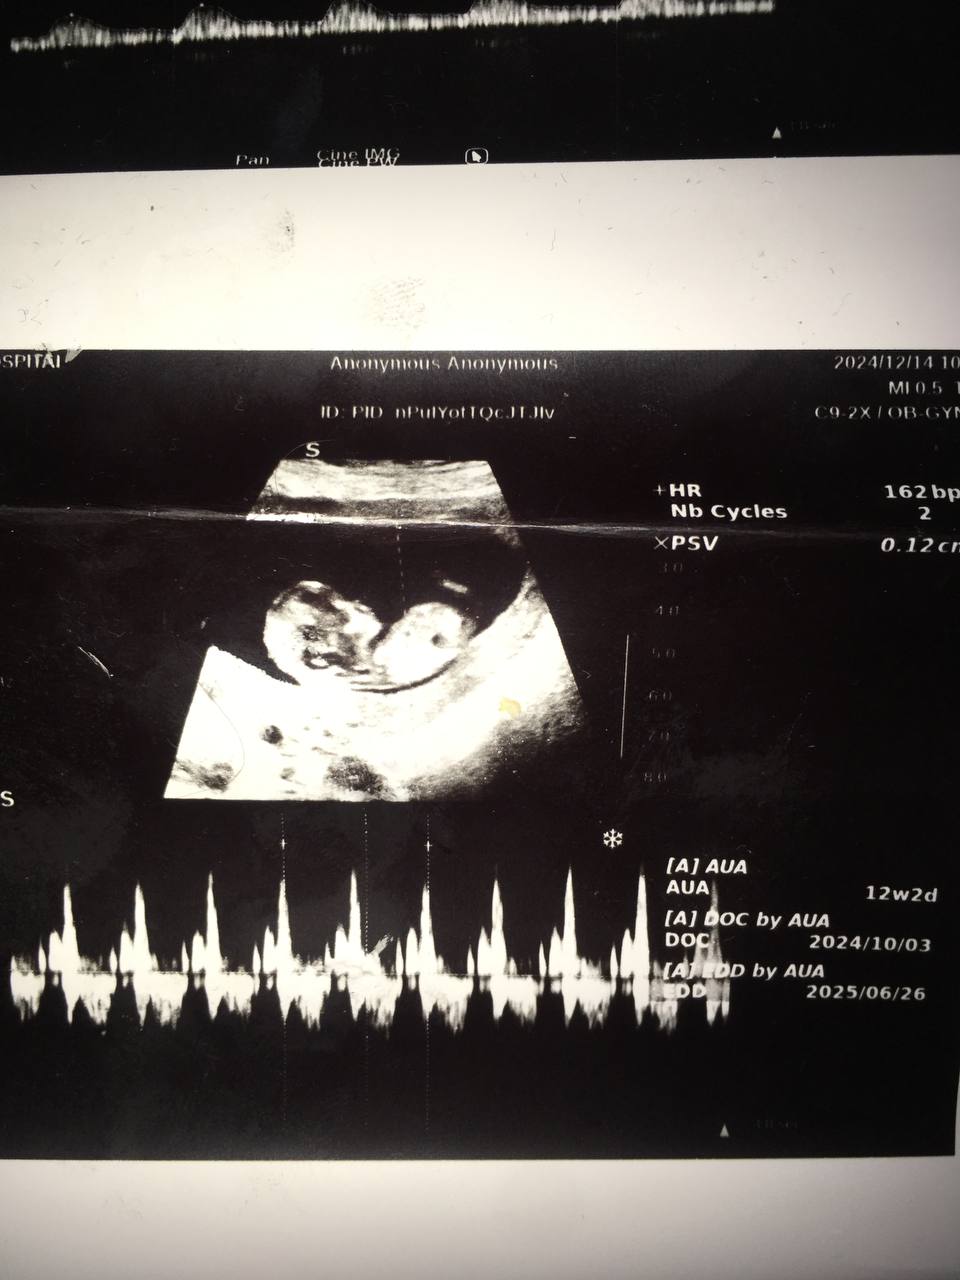

من طبق تقویمم پریودی ۱۱ هفته ۳ روز بودم رفتم ولی سونو گفت ۱۲ هفته ۲ روزی😂 یه هفته هم از تقویمم بزرگ تر بود.